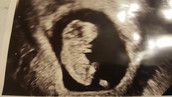

Ansonsten habe ich Mittwoch bei 7+1 den nächsten Termin und hoffe da dann den Herzschlag und das Baby sehen zu können! Bei meinem letzten Termin bei 6+2 hat man leider nur den Dottersack gesehen...

Bei mir hat man bei 6+2 auch nur einen Dottersack gesehen, der am oberen Rand der Fruchthöhle war. Darüber einen Schatten (den ich jetzt nicht gesehen habe), den die FA als Embryo interpretiert hat. Da am Rand hat auch etwas geflimmert, was ich auch gesehen habe (sie meinte das könnte der Herzschlag sein), aber... es war sehr schwierig und sie musste viel an meinem Bauch herumdrücken. Ich denke aber... wo ein Dottersack ist, ist auch ein Embryo :-)